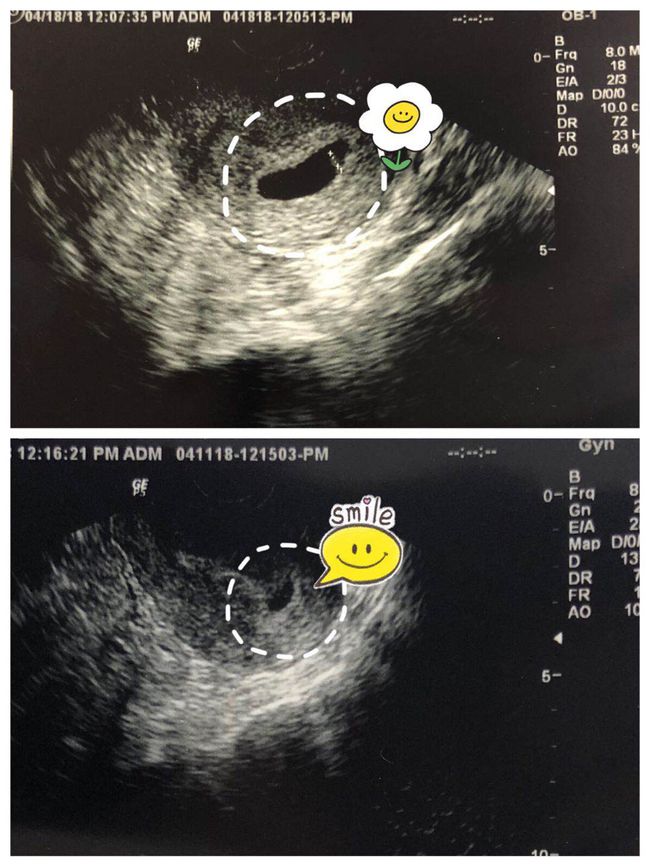

着床出血是指受精卵在子宫内着床过程中,子宫内膜受到刺激而出现的一小部分出血。这种出血通常发生在受精后的一周左右,颜色较淡,持续时间较短,一般不超过几天。

着床出血是怀孕初期的一种生理现象,并不一定意味着胚胎发育异常。然而,如果出现大量出血、腹痛等症状,应及时就医,排除宫外孕、流产等可能。